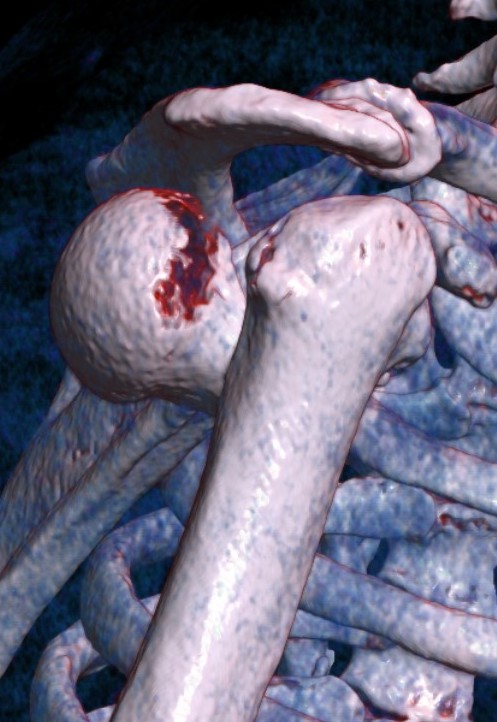

Three part

Three part with greater tuberosity fracture

Three part fracture dislocation anterior

Three part fracture dislocation with anatomical neck

Three part head splitting fracture